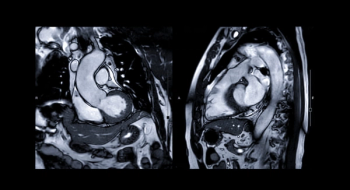

An emerging deep learning algorithm had a lower AUC and sensitivity than urological radiologists for differentiating between small renal masses on computed tomography (CT) scans but had a 21 percent higher sensitivity rate than non-urological radiologists, according to new research.